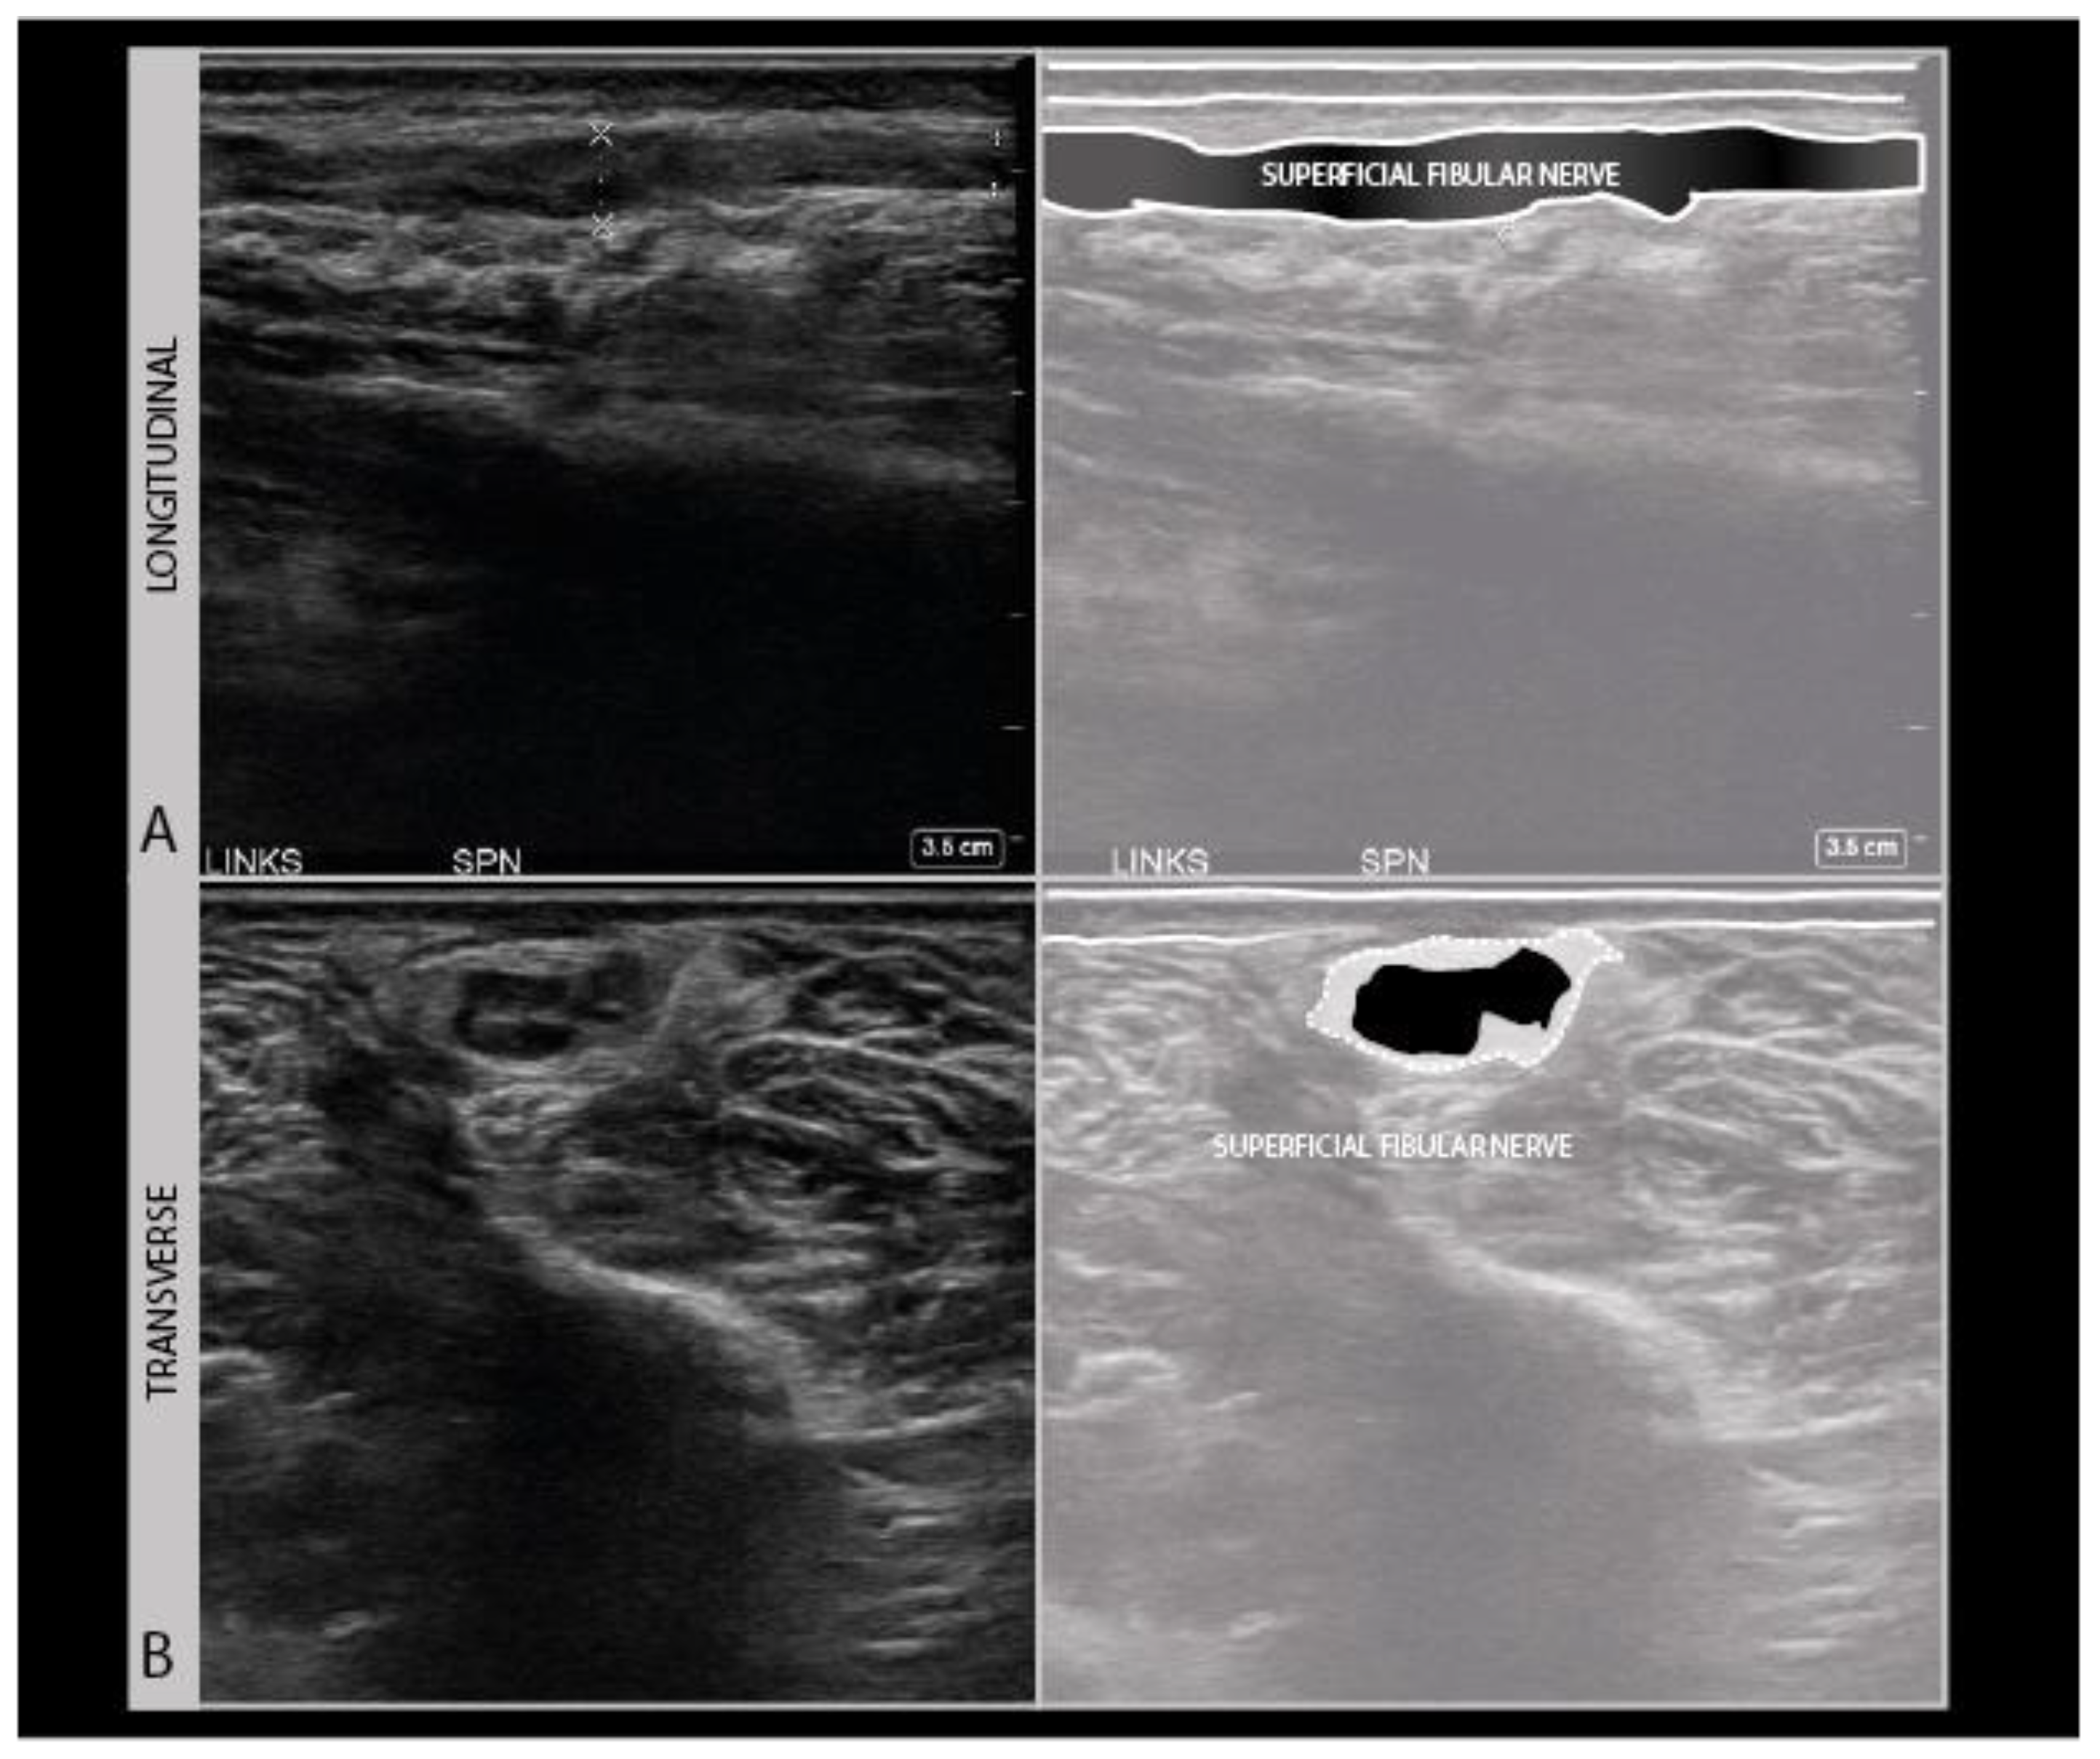

As a standard in neurological nerve ultrasound, transverse imaging is performed for the anatomical identification of the nerve of interest, and to assess its size and architecture for abnormalities. The international agreement is that the nerve size is best measured as a cross-sectional area (CSA) of the nerve traced within the hyperechoic outer epineurial rim [17]. Tracing within the epineurium is the best way to standardize the measurements across patients and over time, as the outer parts of the epineurium blend into surrounding epimysium and fascial structures, which hampers the accurate delineation of the nerve. CSA reference values are available for many nerves [18]. Nerve size increases during growth, so for schoolchildren it is advisable to adhere to a reference that is 50–75% of the adult size depending on age [19].

To assess the nerves for abnormality, it is strongly advised to scan the nerve all the way along its accessible length, looking for sudden changes in size or appearance. When an abnormality is found, it is advisable to also twist the probe 90° around and make a longitudinal image of the lesion site. When measuring neuroma sizes, placing several diameter markers proximal, at and caudal to the lesion site may be helpful (Figure 3).

Longitudinal images are not very good for the identification of the anatomical location, but they are more intuitive for looking at pathology by referring physicians (or patients). It is advisable to annotate images with sparse text to indicate the site, including a nerve name abbreviation such as “MED” for the median nerve, and an indicator for left/right, distal/proximal, etc.). For any nerve that could require surgical intervention, it is recommended to measure the site of abnormality in reference to a recognizable anatomical landmark (e.g., “5 cm distal from the intermalleolar line, 2 cm lateral from the midline” etc.). We strongly recommend making a short ultrasound video scanning from the proximal across a lesion site to a distal one, as ultrasound videos are much easier to interpret afterwards than still images. Finally, the images should be saved to a network location or printed to be saved with the patients’ health records.

Scars also indicate the direction of tissue interruption and whether that may have impacted the nerve or not. They also show possible areas of tissue retraction in surgical cases of iatrogenic nerve injury. Traction on wound edges is an often overlooked but not infrequent reason for iatrogenic nerve damage and is relatively common in certain procedures such as lymph node excision in the posterior cervical region with damage to the accessory nerve mentioned earlier, and the surgical decompression of anterior tibial compartment syndrome with damage of the superficial peroneal nerve (Figure 10).

Figure 10.

Disorganized and hypoechogenic superficial peroneal nerve neuroma in the distal lower leg in longitudinal (A) and transverse (B) direction; traction injury following surgical decompression with fasciotomy for anterior tibial compartment syndrome.

Many sensory peripheral nerves run in the skin and subcutaneous areas that form a surgical approach route to the operation. These nerves are therefore at risk of iatrogenic injury. Well known examples are the patellar branches of the saphenous nerve during knee surgery, the abdominal intercostal nerves during laparotomies, the superficial peroneal nerve during anterior tibial compartment syndrome release, the sural nerve during lateral ankle surgery, and the accessory nerve during lymph node biopsy. The course of these nerves makes them vulnerable to direct damage during incision, traction injury from skin and subcutis retractors, and stretch by the manipulation or compression of the joint to gain surgical access, or during the surgery itself with the use of clamps or osteosynthesis material [8,9].

Iatrogenic nerve injury is now considered a calculated risk in many procedures, that the patient should be informed about before the surgery. With correct anatomical knowledge of the anatomical course of the nerve, the surgeon can reduce the risk of damaging it. However, the exact course of these superficial nerve branches and the level of bifurcations into their terminal branches can be highly variable due to anatomical variation [51]. Nerve ultrasound offers the opportunity to evaluate and annotate the exact anatomic course of the nerve preoperatively. Some surgeons already use this preoperative nerve ultrasound imaging to minimize the tissue dissection and operating time, but somewhat ironically this is mostly done for the treatment of neuroma following iatrogenic nerve injury. [52,53]. There is not yet much information on the use of preoperative ultrasound to prevent nerve injury, but a few papers illustrate the useful role nerve ultrasounds can play in preventing iatrogenic injury [54,55]. Nerves at risk for iatrogenic injury that can be easily located and marked as pre-operative with nerve ultrasound, are summarized in Table 1 [9,56,57,58]. We would heartily recommend the use of ultrasound during the presurgical planning to reduce the incidence of iatrogenic nerve injury, as this would significantly reduce the burden of this infrequent but debilitating peri-operative complication in terms of patients’ distress, disability and litigations [9].